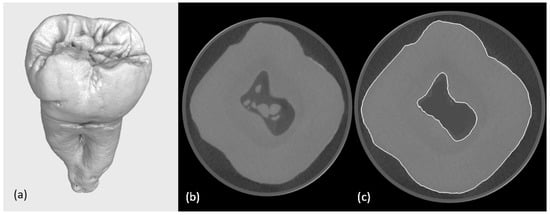

A further inspection of the segmented root canal system revealed morphological irregularities and surface noise that would have compromised the final mesh. To address this, a Taubin smoothing algorithm was applied to the preliminary mesh [16,17]. This filter effectively reduced geometric complexity while preserving surface integrity and preventing mesh shrinkage (Figure 2). A clean surface mesh was generated and exported in STL format. Initial micro-CT scanning of the tooth specimen yielded a high-resolution polygonal model comprising 504 and 300 triangles. The application of Meshmixer effectively addressed various mesh defects, with many minor imperfections automatically corrected. More complex topological errors, however, necessitated targeted manual intervention. Following these corrective procedures, the polygon count was systematically reduced to approximately 30,000 triangles. This decimation process was meticulously monitored to ensure the precise preservation of all critical anatomical features, maintaining their clear expression for accurate downstream analysis.

Figure 2. Demonstration of the refinement. Situation before (white contour surface determination) and situation after (yellow contour).